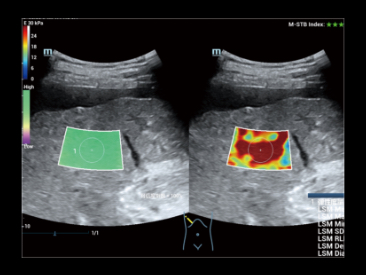

Inteligentna ocena st?uszczenia w?troby poprzez automatyczne obliczanie stosunku jasno?ci w?troby do kory nerek w trybie B.

Obrazowanie fuzyjne technik? 3D

Obrazowanie fuzyjne technik? 3D

Kompensacja oddechowa

Kompensacja oddechowa